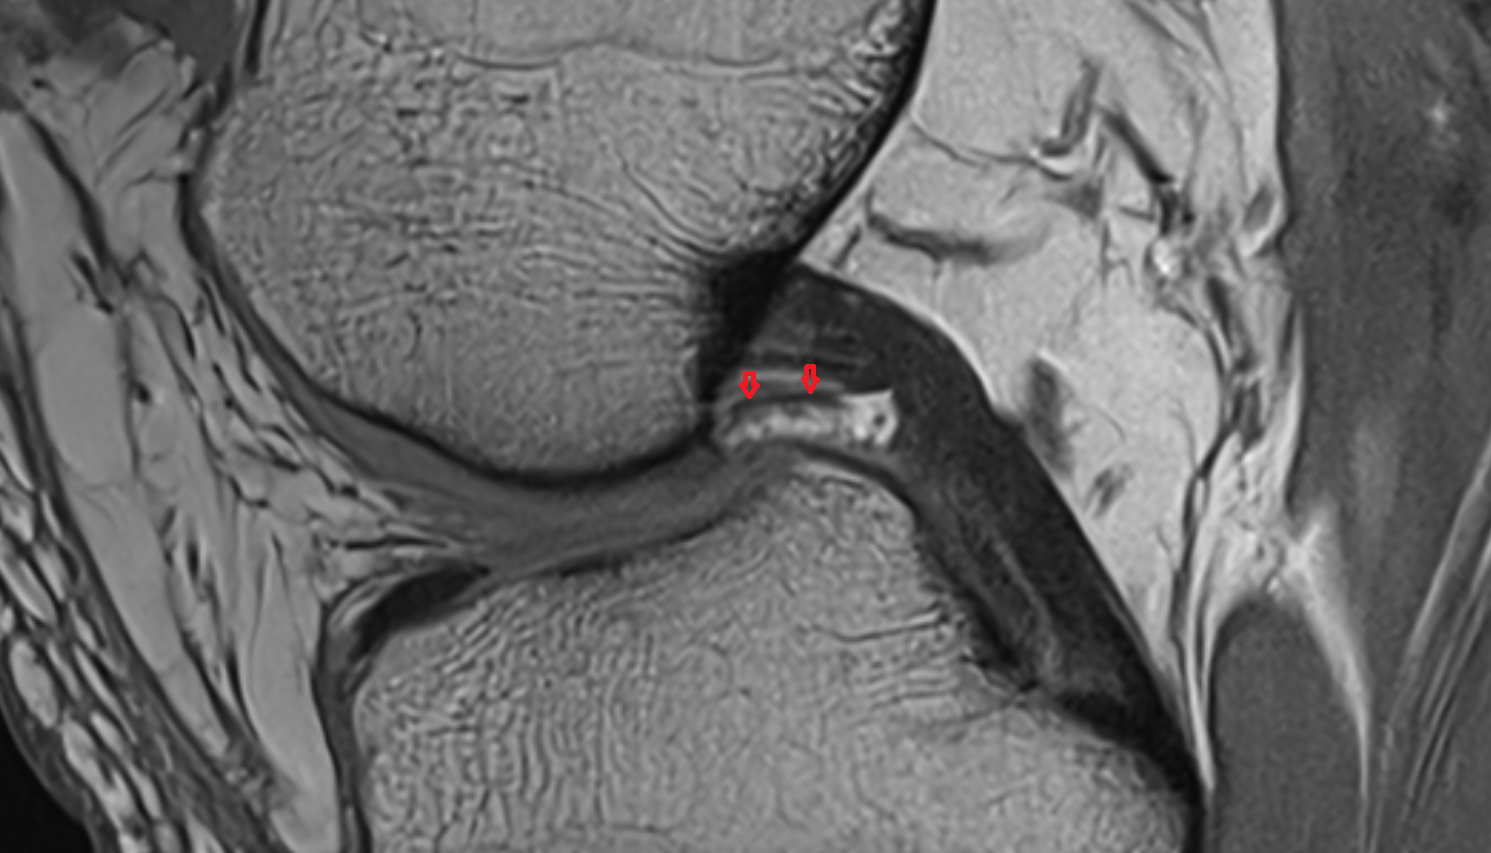

- Knee Joint